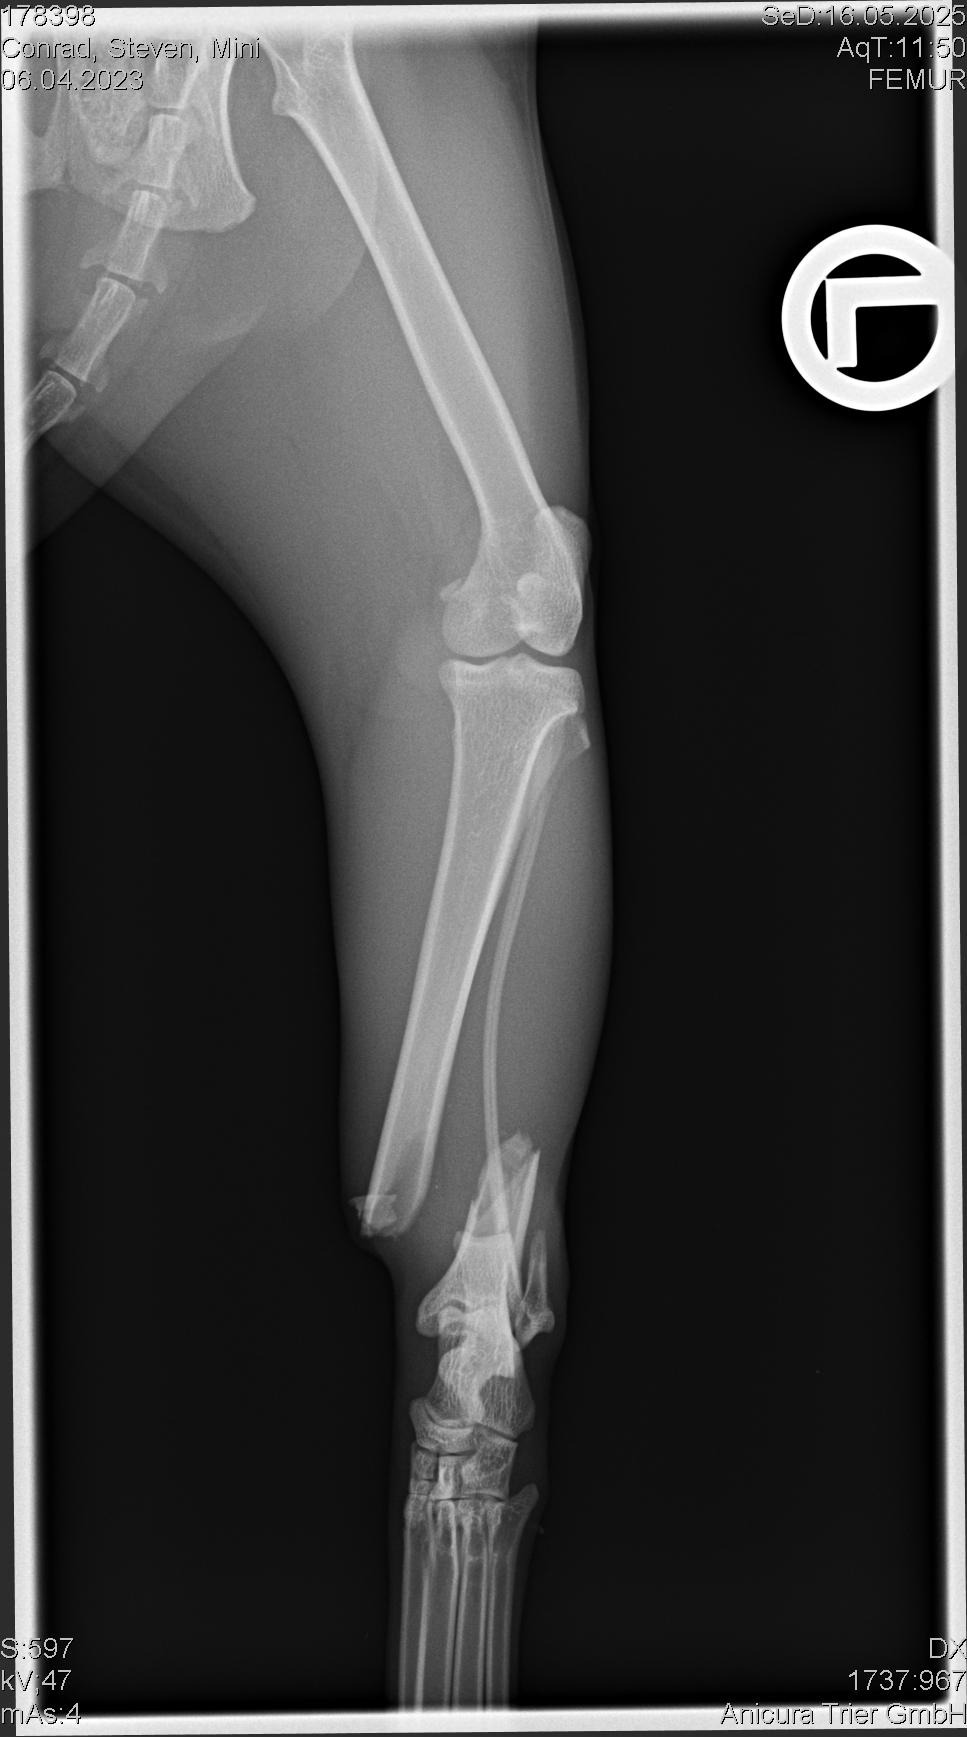

Am 16. Mai 2025 musste Mini aufgrund einer schweren Verletzung am Sprunggelenk operiert werden. Die Operation war aufwendig – es wurde eine Metallplatte eingesetzt, und sie musste anschließend acht Wochen lang in strikter Boxenruhe verbringen.